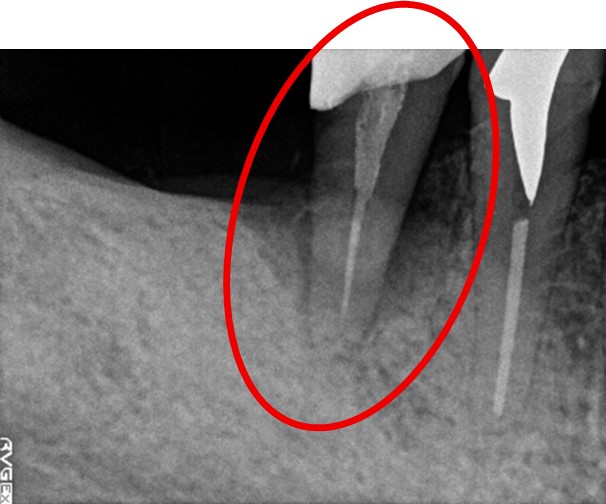

男性 Eさん 80代 (インプラント)

主訴

左上2本が動いていて、噛むと痛みがある。歯がないところに歯を入れたい。

治療内容

左上第二小臼歯と第一大臼歯の歯根が破折していたため、保存することができず抜歯しました。第一小臼歯は、すでにありませんでしたので、2本抜歯後3本欠損のところにインプラントを2本埋入しました。

所感

2006年10月に右下と左下の欠損部分にインプラント治療をしました。今回も左上の歯を失ったところは、インプラント治療を希望されました。

インプラント2本:¥363,000✕2本=¥726,000(税込)

ポンティック1本:¥115,500(税込)

合計:¥841,500(税込)

Before

※赤丸は、歯根が破折していたため抜歯しました

※黄色丸は、2006年10月に埋入したインプラント

After

※緑丸は、今回埋入したインプラント